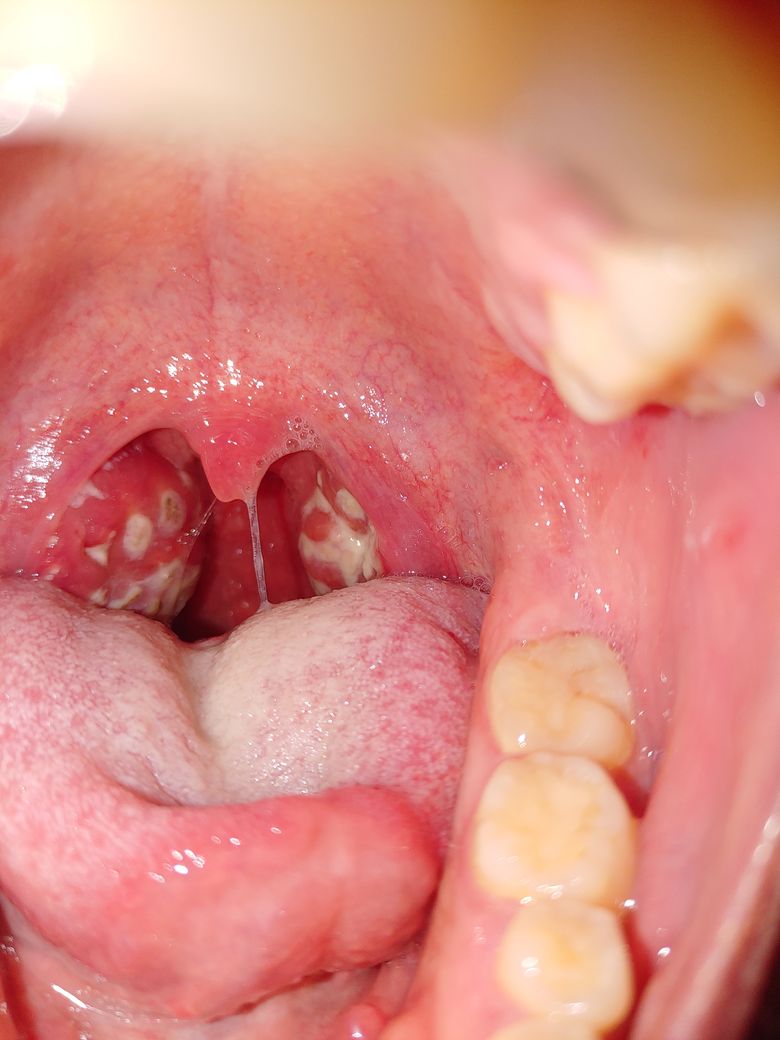

+아래 사진은 올해초 편도염이 심하게 왔을때에요

이때도 통증은 없었고 열만 났어요.

• 1번 째 사진

사진만 보면 지금은 편도염이 심한것은 아닙니다. 집에서 소염진통제 정도만 드시면서 지켜보셔도 될것 같습니다.

과거 사진에서와 달리 현재는 편도염이 두드러지지 않는 상황이며 인두염이 의심되는 정도입니다. 호흡기 감염증 증상이 코로나 바이러스 감염증과 거의 유사하므로 확인하고자 하신다면 자가진단키트를 사용해보시거나 신속항원검사를 받아보시는 것이 가장 정확하겠습니다.

뚜렷한 편도염은 관찰되지 않는 상태이며, 아마도 감기가 아닐까 추정이 됩니다. 증상만으로 감기, 독감, 코로나를 구분할 수 없으면 필요 시 PCR검사를 하게 됩니다.